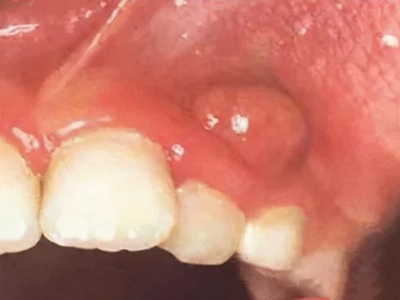

根尖囊肿是成牙组织囊肿中最常见者,多发生在上列切牙、尖牙或磨牙等牙根的唇面。由于根尖肉芽肿、慢性炎症的刺激,引起牙周膜内的上皮残余增生。增生的上皮团中央发生变性与液化,周围组织液不断渗出,逐渐形成囊肿,故亦可称根尖周囊肿。

根尖囊肿生长缓慢,病人多无自觉症状。口腔检查可见患牙有龋损或其他非龋性牙体病,或牙冠变色失去光泽。叩诊可有不适感,温度测验患牙无反应。囊肿大小不等,小囊肿不易被发现。囊肿发展较大时,可见根尖部隆起,扪诊时有乒乓球感,这是由于囊肿外围只有一层极薄的骨板存在。大囊肿还可压迫牙根,使邻牙移位。